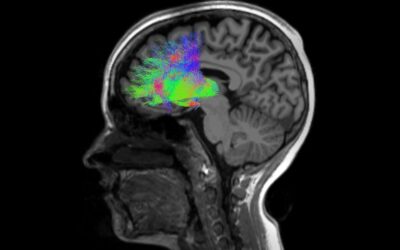

Paper Alert! Revealing the Neural Basis of Executive Dysfunction in Schizophrenia

I would like to highlight a new paper that we published in collaboration with Neil Woodward’s lab at Vanderbilt, co-lead by research professors Anna Huang (Vanderbilt) and Ralf Wimmer (Tufts), with contributions from postdoctoral fellow Norman Lam and MSTP student...